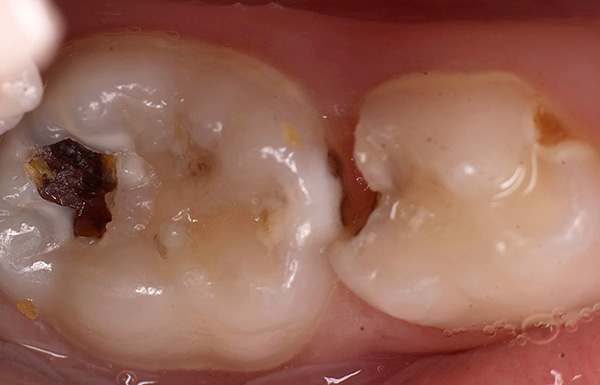

Às vezes, existe um conceito absolutamente errado dos pais de que, como os dentes de leite são temporários, você não precisa cuidar deles. Eles dizem que vão cair de qualquer maneira, e então já será possível fazer uma higiene mais completa. Com essa abordagem, a condição dos dentes do bebê em um bebê pode ser verdadeiramente catastrófica:

É importante entender que problemas na mordida do leite inevitavelmente terão um efeito prejudicial na mordida permanente e, às vezes (mesmo com processos inflamatórios graves), até os rudimentos de futuros dentes permanentes podem ser danificados.